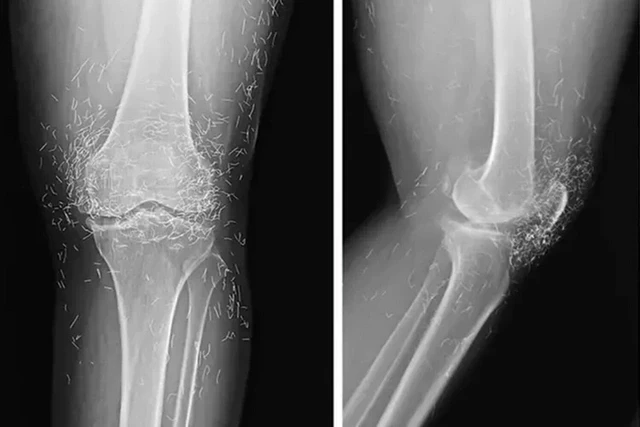

Rentgen müayinəsi zamanı sümüklərin qalınlaşması və deformasiyası, osteoartritin tipik əlamətləri, eləcə də diz oynağının ətrafındakı toxumaya yerləşdirilmiş yüzlərlə qızıl fraqmentlər müəyyən edilib.

Mütəxəssislərin fikrincə, qızıl saplarla akupunkturun sübut edilmiş effektivliyi yoxdur və özündə ciddi risklər daşıyır:

"Qızıl saplar kistalara səbəb ola, toxumaları zədələyə, bütün bədənə miqrasiya edə bilər. Bundan əlavə, metalın yerdəyişməsi və damarların zədələnməsi riski səbəbindən onların mövcudluğu MRT-ni son dərəcə təhlükəli edir", - deyə həkimlər vurğulayıblar. lent.az